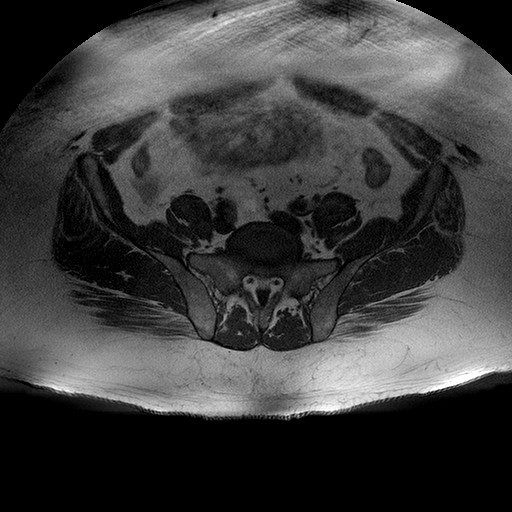

Esami: RMN BACINO

T1W_TSE

Evidenti e simmetriche alterazioni osteofitosiche in regione coxo femorale con riduzione delle rime articolari. Degenerazione completa del cercine glenoideo. Non attuali segni di versamento articolare. Non segni di edema osseo che escludono attuale algodistrofia od osteonecrosi. Lieve e simmetrica riduzione del trofismo della muscolatura glutea.